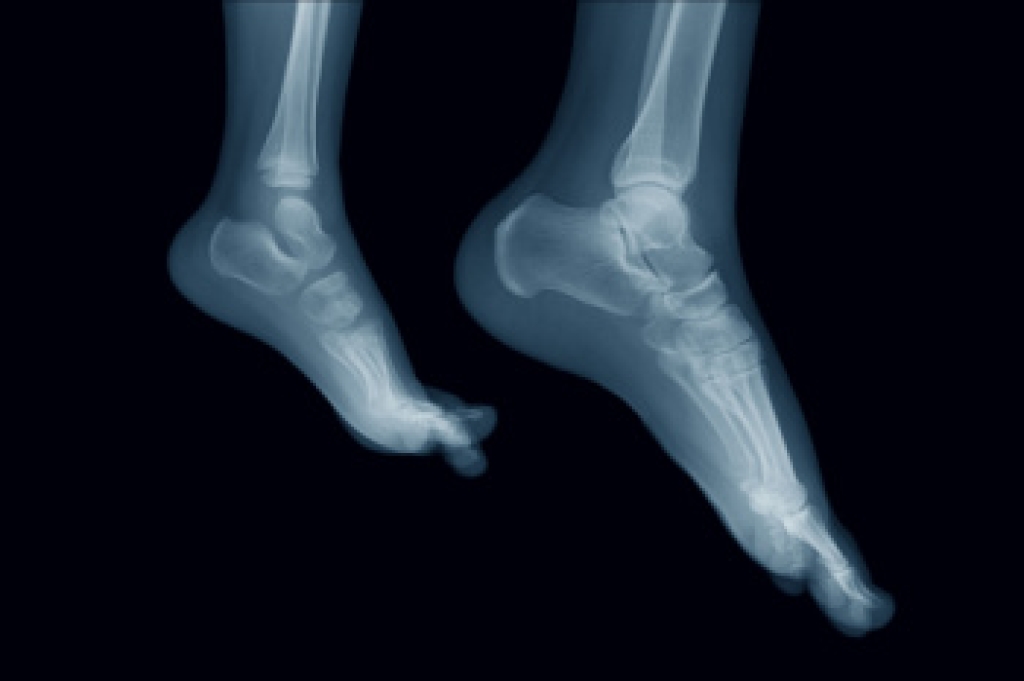

The foot is a complex structure made of tarsals, metatarsals, and phalanges that work together to support movement and balance. The tarsals form the back of the foot and help create stability for standing and walking. The metatarsals form the middle of the foot and distribute weight evenly with each step. The phalanges are the toe bones that help with push off and balance during movement. All these parts work in harmony with muscles, tendons, and ligaments to absorb shock and keep the body aligned. When any part is strained or out of balance, pain and mobility issues can develop. A podiatrist can evaluate the structure of the foot, address problems, and recommend treatments that improve comfort and function. If you have foot pain, it is suggested that you consult a podiatrist who can treat various foot conditions.

To figure out the cause of foot pain, podiatrists utilize several different methods. This can range from simple visual inspections and sensation tests to X-rays and MRI scans. Prior medical history, family medical history, and any recent physical traumatic events will all be taken into consideration for a proper diagnosis.